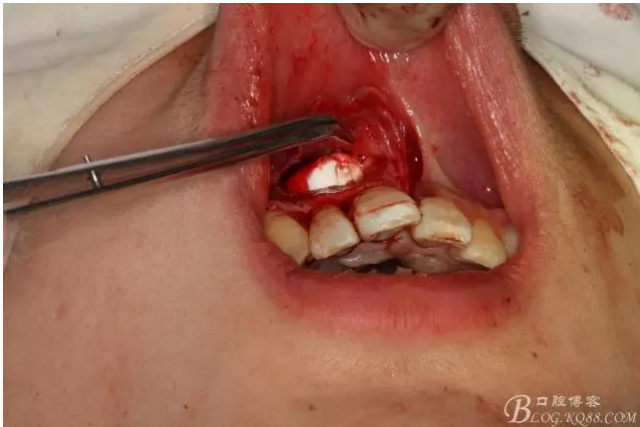

圖6.超聲骨刀切除根尖3mm。

圖7.切除根尖3mm的影像

圖8.根尖區(qū)超聲倒預(yù)備3mm

圖9.去除根尖3mm牙膠。

圖10.超聲骨刀去除的牙膠